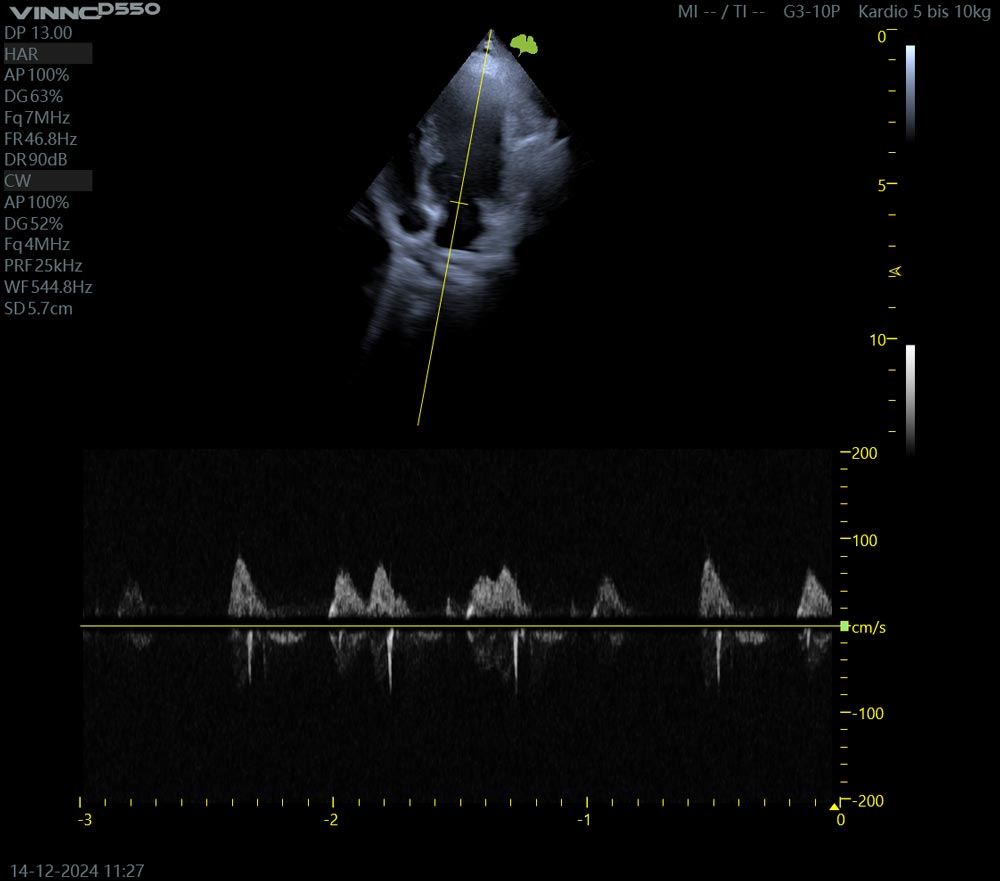

Die Untersuchung des Herzens mittels Ultraschall, Echokardiographie genannt, ermöglicht eine präzise Darstellung der Herzstrukturen und der Herzleistung. Wir können die Herzklappen der beiden Kammersysteme genau darstellen, ihre Dichtigkeit mit dem Farbdoppler untersuchen und die Auswurfleistung des Herzens mit dem Spektraldoppler hochauflösend darstellen. Ein mitlaufendes EKG zeigt genau, wann sich Klappen schließen, wie sich der Herzmuskel kontrahiert und vieles mehr.